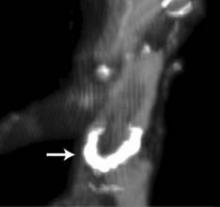

Atherosclerosis is usually considered to be related to contemporary risk factors such as smoking, obesity and lack of exercise. However, researchers suggest that high prevalence of atherosclerosis in pre-modern humans may support the possibility of a more basic human predisposition to the disease.